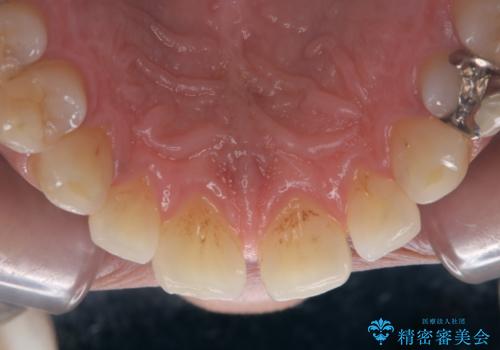

着色(ステイン)が裏表と付着し、全体的に歯石やプラーク(細菌の塊)も付着していたのでPMTC60分コース(自費クリーニング)を行いました。

クリーニングで、汚れを除去した際に、古い詰め物の色がより目立ってきたため、今後やり替えすることになりました。